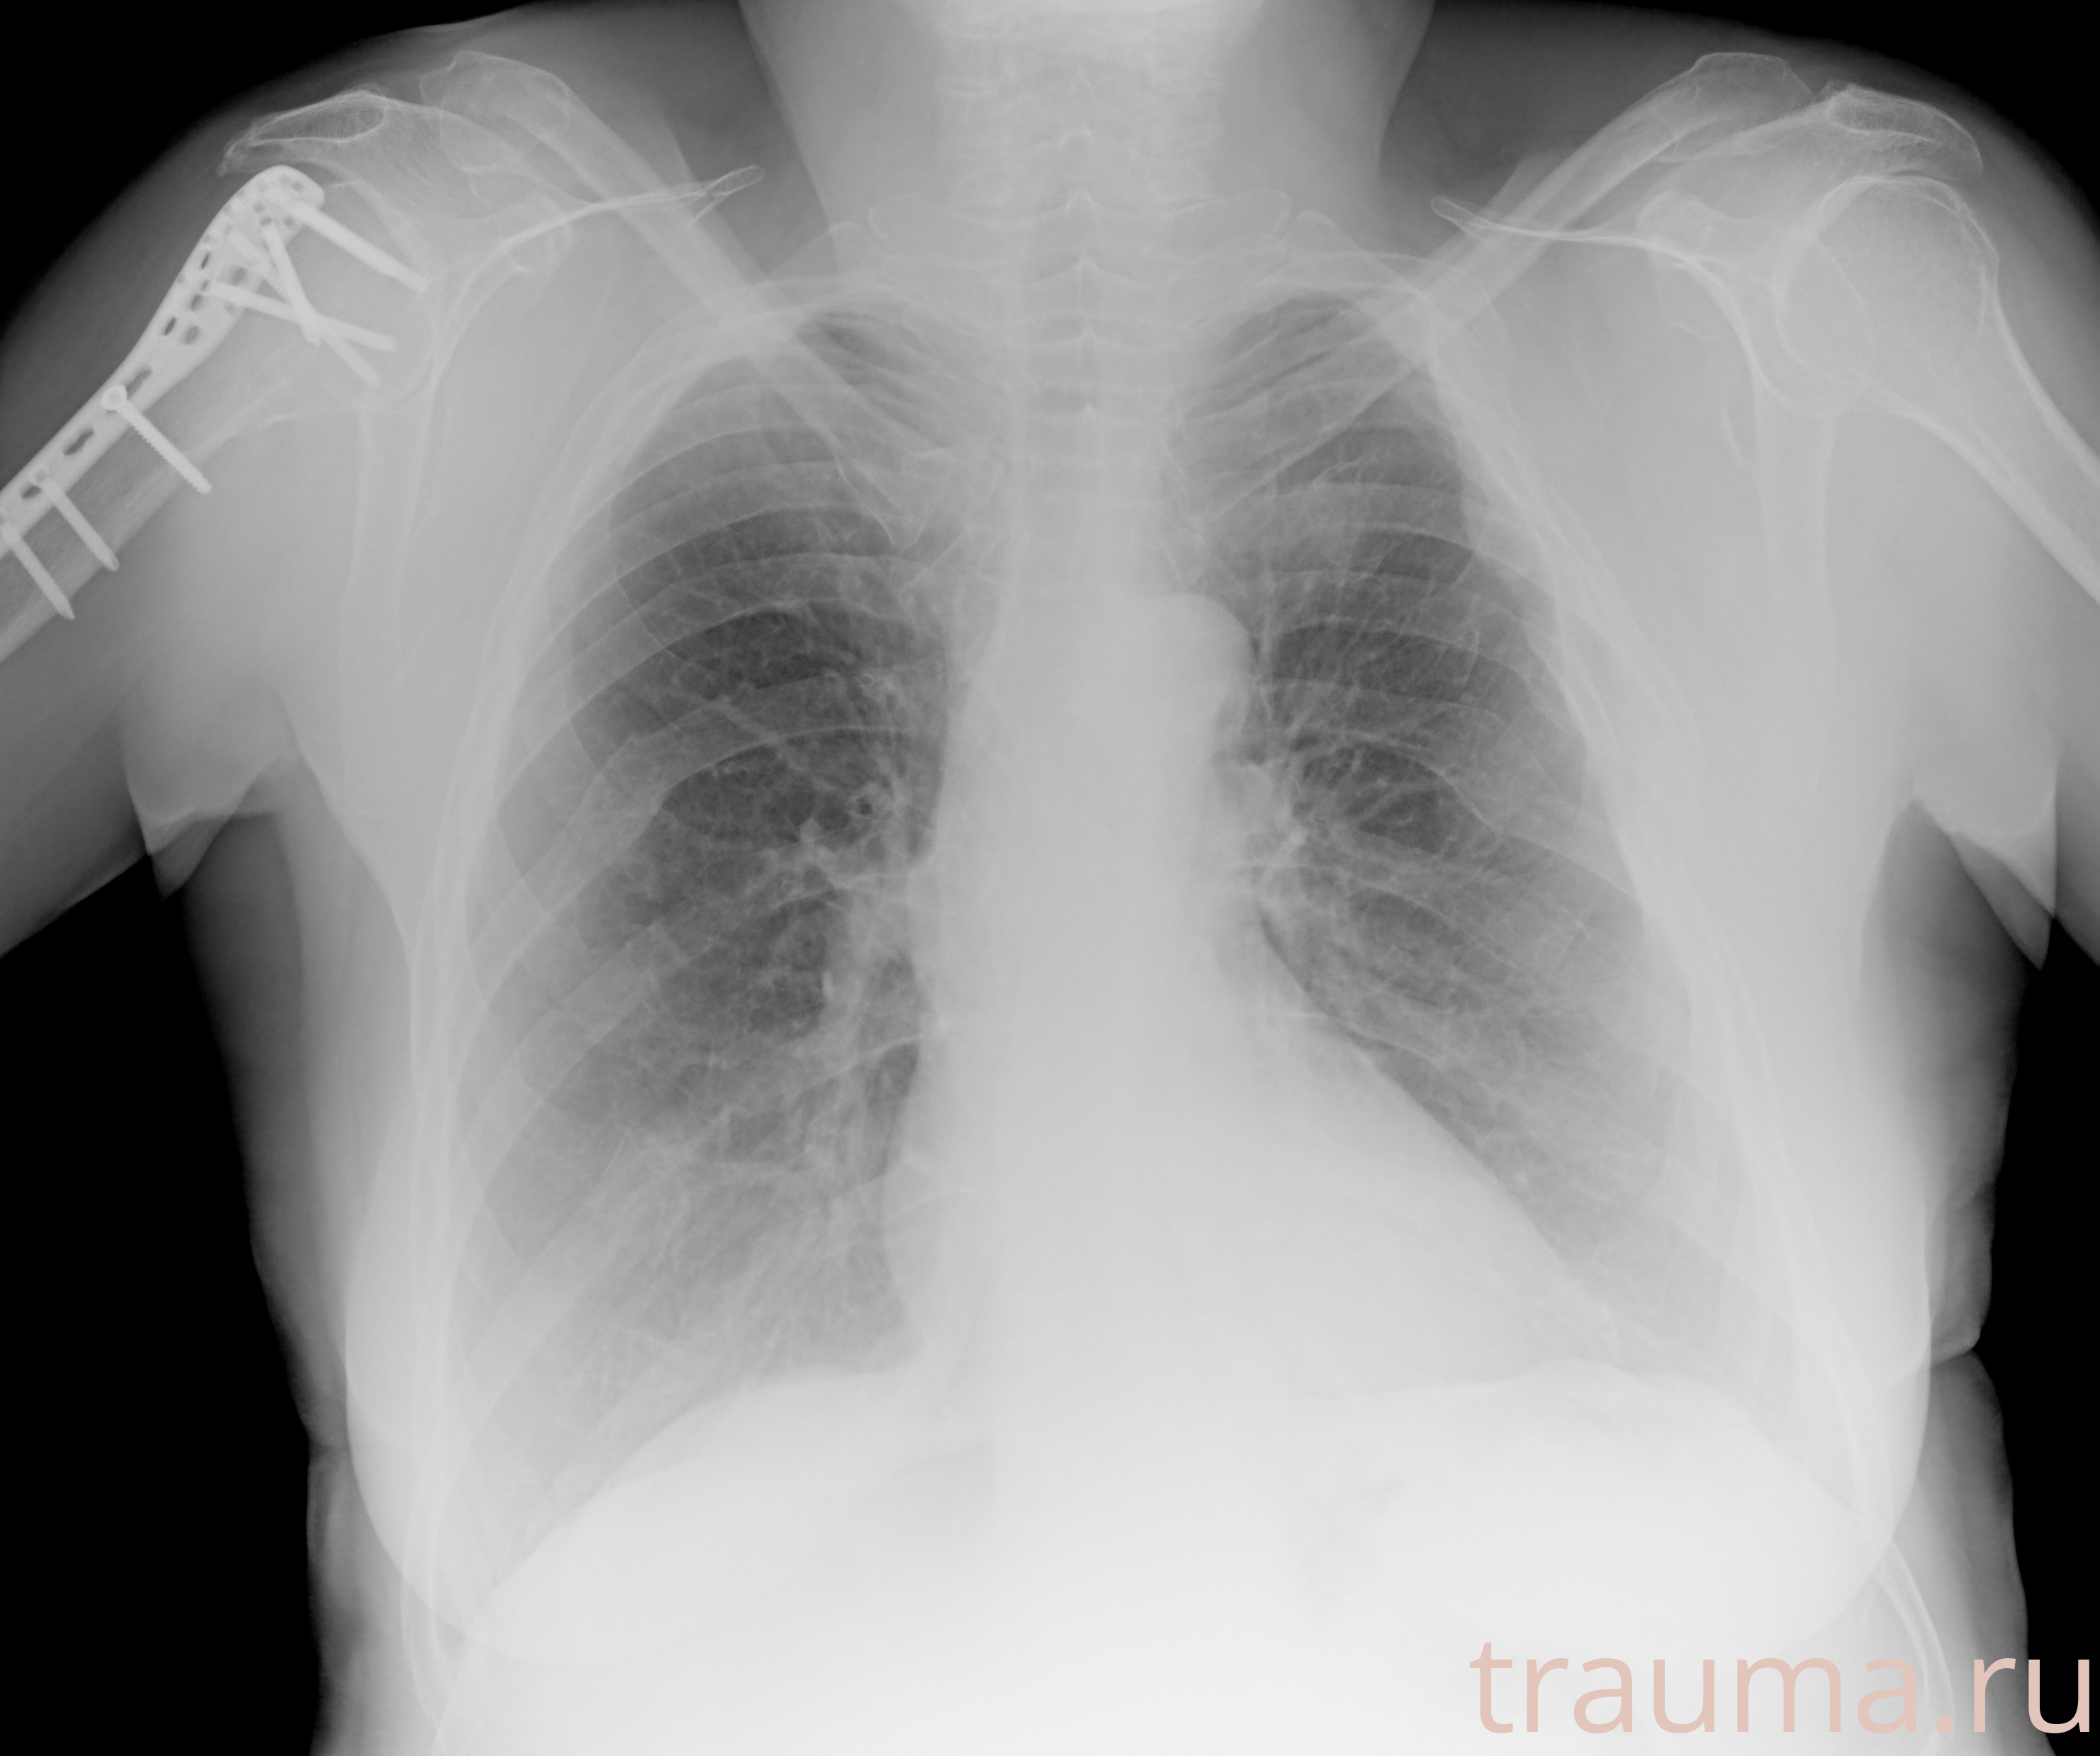

Рентгенограммы

Рентген на дому: по вашему адресу приезжает врач-рентгенолог, травматолог-ортопед с мобильным рентгеновским аппаратом, проводит диагностику травмы или заболевания, делает необходимые рентгенограммы, дает рекомендации по дальнейшему лечению. Получить качественные снимки в домашних условиях возможно благодаря уникальной методике, разработанной МосРентген Центром для института  Склифосовского

Яркость: 1   Контраст: 1   Инвертировать: 0 Увеличение: 1

Перетаскивайте мышь вверх/вниз для контраста, влево/право для яркости. Прокрутка колесом изменяет масштаб. Нажмите Сбросить для возврата к исходному изображению. При увеличении держите мышь в той области, которую хотите рассмотреть.